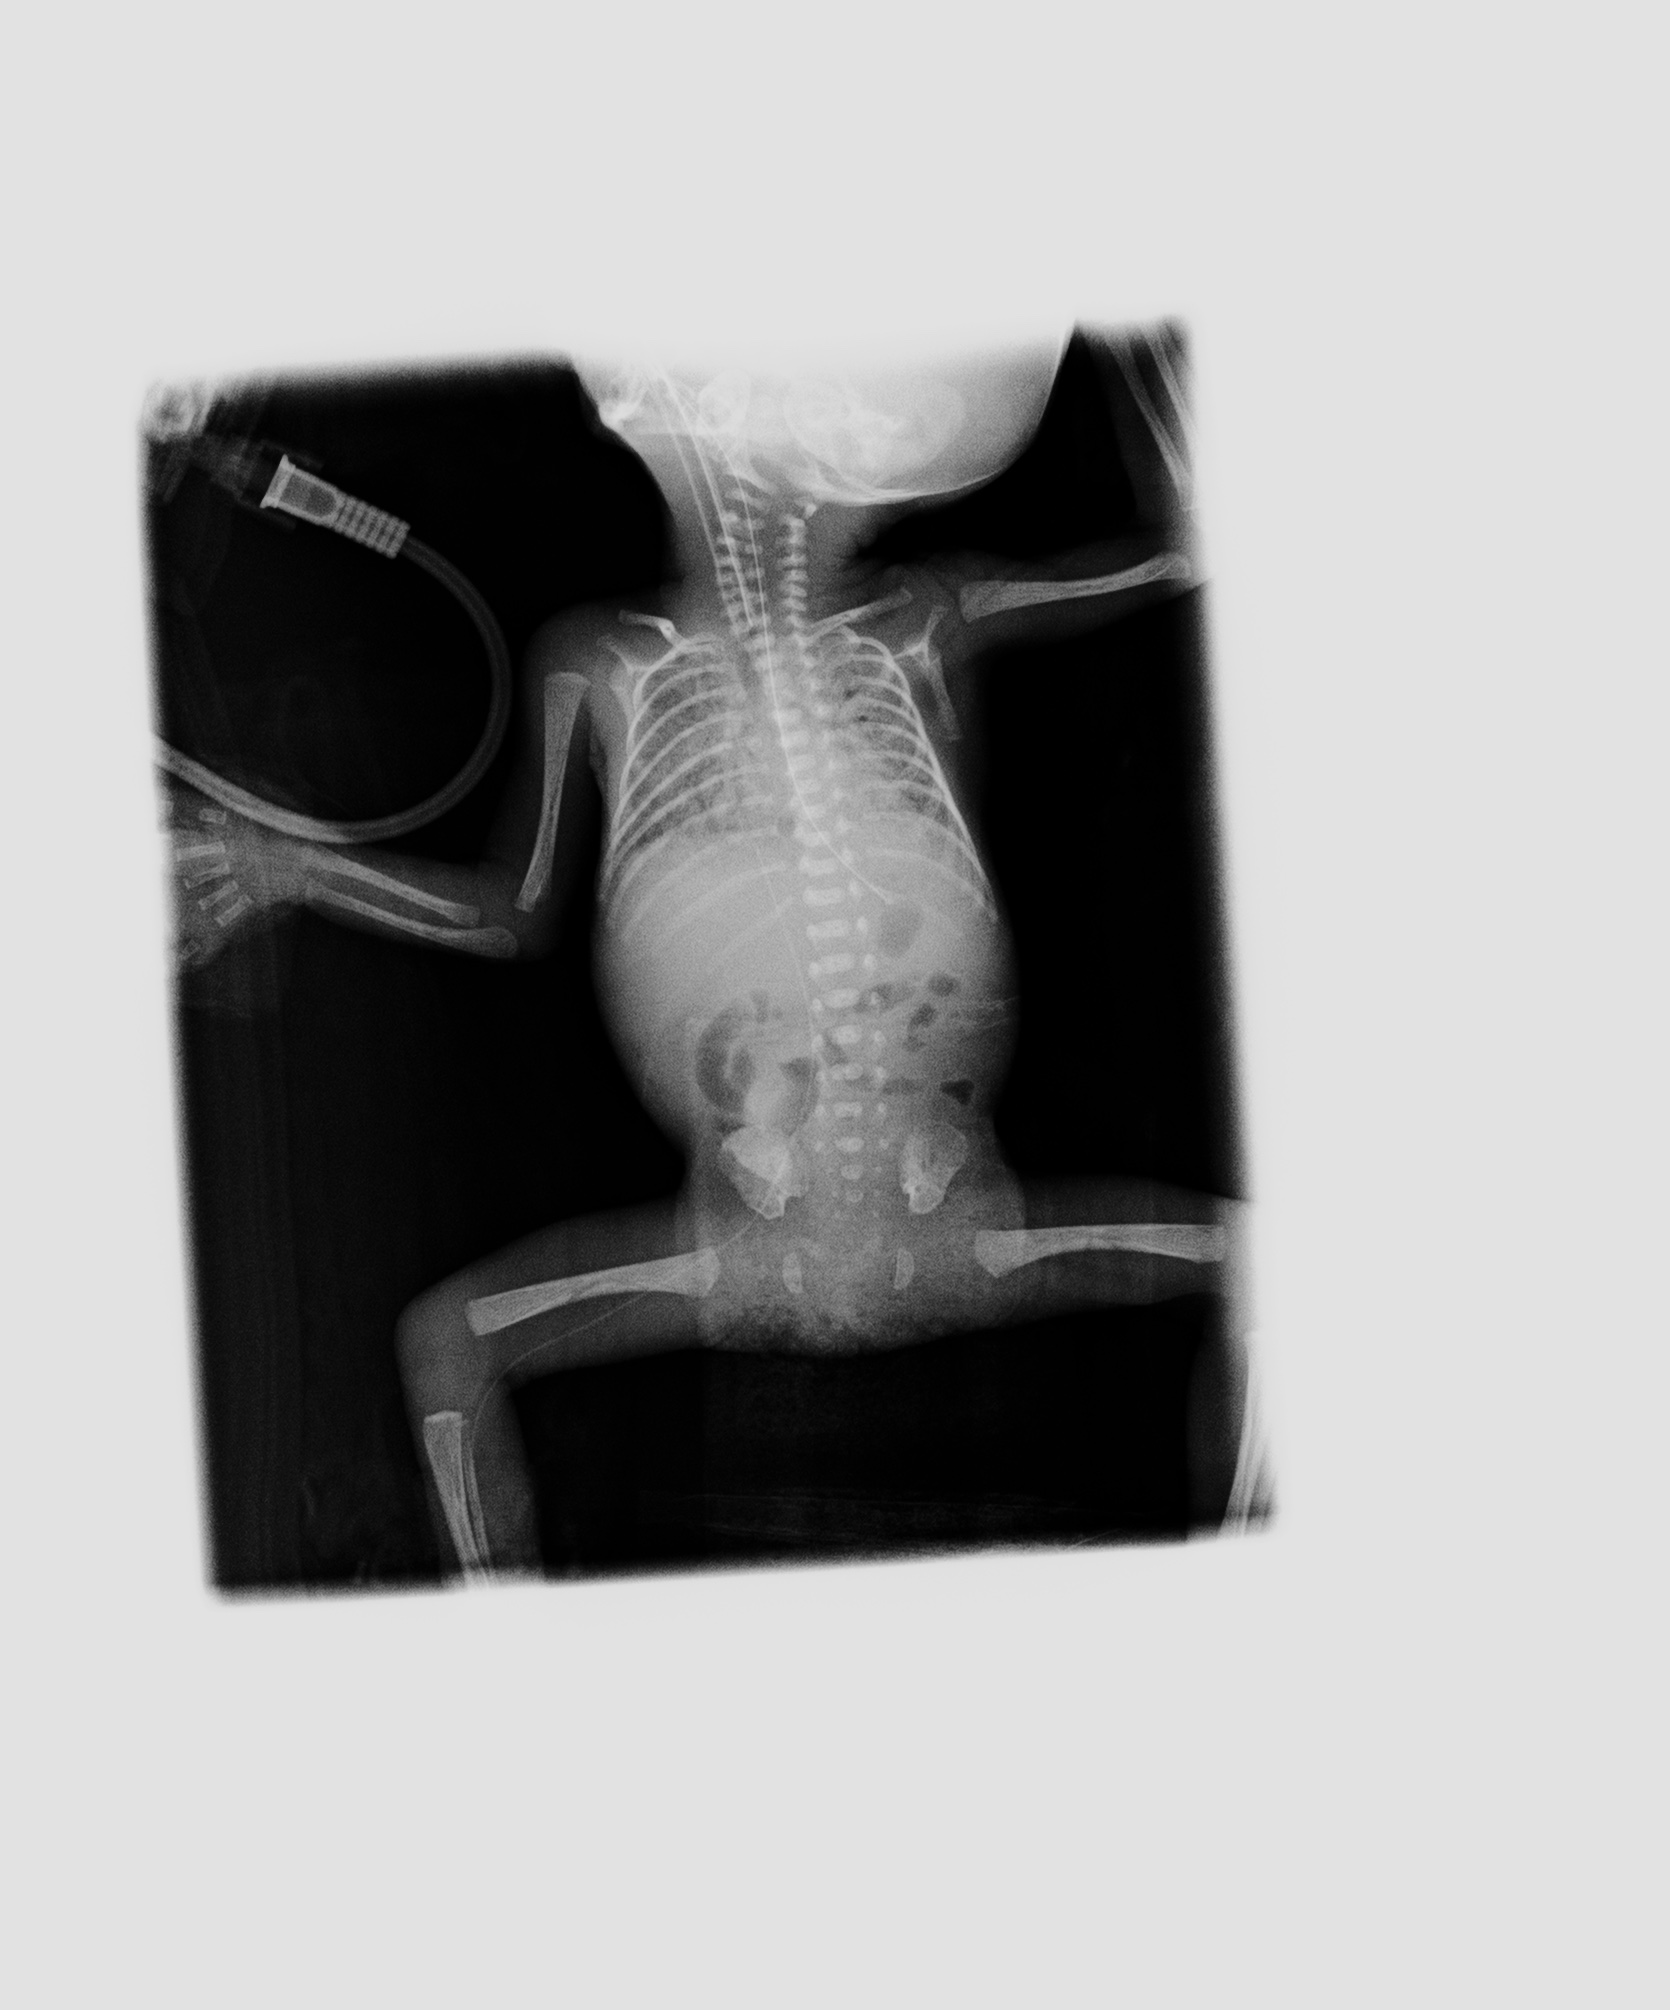

• (生前:○月24日13時44分、X線撮影)サーファクタント投与前の撮影と思われる。両側肺の volume 低下、透過性低下があり、RDS の状態にあると思われる。上腕骨の骨端線の骨濃度が骨幹部と不釣り合いに高く見える。非特異的所見ではあるが、すでに胎内で一定期間の侵襲が加わっていたことを示唆する。 この時点では carina での左右主気管支の分岐角は大きくなく、その後の撮影と対照をなす。この後心拡大が進行していったことを示している。

• (生前:○月25日10時19分、X線撮影)サーファクタント投与後の撮影と思われる。右肺は一定の含気が得られたが、肺野には微細な粒状影が蜜に分布し、依然として RDS 相当の状態にあると推測させる。 左肺はより末梢肺の拡張が不良で white out している状態。気管支の断面が大きく陽圧呼吸下にあることを示すが、空気漏出は生じていない。 気管内チューブ、右下肢からの PI カテーテル、胃管などのデバイス類の走行経路には異常なし。

• (生前:○月25日22時52分、X線撮影)右肺は前日より伸展し、air entry が得られている。肺紋理の血管断面が、いわゆる white dots として増強しており、肺の高血流状態を示す。左肺の air entry は昨日よりは良くなっているが、上葉の一部に留まっており右に比べて含気不良である。

• (生前:○月26日11時20分、X線撮影)両側肺は透過性が前日より高まっているが、25 日 10:19 時点のような RG パターン様の微細粒状影があるように見える。

• (生前:○月26日11時20分、X線撮影)両側肺の含気低下進行。左肺はほとんど含気を失っている。右肺でも斑状影が癒合するように拡大している。臨床的に観察された肺出血の際の胸部所見としては整合する所見で ある。気管の断面は拡張しており、陽圧がかけられていることを示唆しているが、この時点でも明らかな気道系からの空気漏出はない。食道内の空気が頸部に見える。